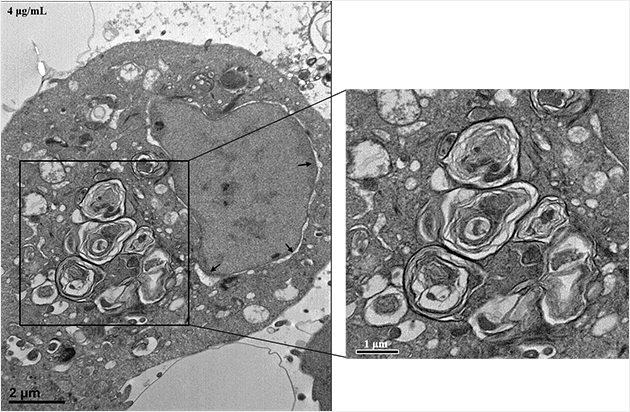

동서의학연구소 박은정 교수가 코로나19로 사용이 급증한 살균·소독제에 호흡기가 노출되면 폐 질환을 유발할 수 있다는 연구 결과를 발표했다. 사진은 탈이온수에 분산된 DDAC의 전자 현미경 사진. 동서의학연구소 박은정 교수, 코로나19로 사용 증가한 살균·소독제 사용 위험성 규명 연구 관련 논문 <Toxicology and Applied Pharmacology> 온라인판 게재 동서의학연구소 박은정 교수가 코로나19 팬데믹으로 사용이 급증하고 있는 살균·소독제의 호흡기 노출이 폐 질환을 유발할 가능성이 있다는 연구 결과를 발표했다. 이번 연구에서 박은정 교수는 ‘염화디데실디메틸암모늄(Didecyldimethylammonium chloride, DDAC)’에 지속적으로 노출될 경우 체내 축적 및 폐질환 유도 가능성을 배제할 수 없고, 이를 위한 추가 연구가 필요하다고 강조했다. 관련 연구 결과는 지난 8월 14일(금) ‘라멜라 구조의 형성이 염화디데실디메틸암모늄으로 인한 독성 반응 개시인자일 것이다(Formation of lamellar body-like structure may be an initiator of didecyldimethylammonium chloride-induced toxic response)’라는 제목의 논문으로 SCI급 저널인 <Toxicology and Applied Pharmacology>의 온라인판에 게재됐다. 살균제 성분 중 DDAC 관련 연구 진행, 관련 위험성 연구 거의 전무해 박은정 교수는 그간 가습기 살균제 사건과 관련된 물질에 관한 연구를 계속해왔다. DDAC는 세균이나 바이러스와 같은 미생물 확산 차단을 위해 사용하는 물질로, 미국 환경청에 등록된 4가 암모늄 계열 살균·소독제이다. 목재나 건축 용품, 물탱크 같은 산업용 물품과 가습기나 세탁기 같은 주거용 제품의 방부제나 소독제, 항생제로 많이 사용된다. 그동안 호흡기 노출과 관련된 연구 결과가 거의 전무한 성분으로 박 교수는 이에 대한 위험성 판단을 위해 연구를 진행했다. DDAC는 지난 2006년 이후 우리나라에서 발생한 가습기 살균제 사건의 주요 성분 중 하나로 박 교수는 2016년부터 이 사건과 관련된 물질을 연구했다. 이번 연구에서는 인간기관지 상피 세포(BEAS-2B)와 실험용 쥐를 사용해 폐 질환 유도 가능성과 그 독성 기전을 연구했다. 연구 결과 DDAC는 4μg/mL 농도에서 세포 생존율을 급격하게 감소시켰고, 세포 내 소기관 손상과 함께 세포 자살과 세포막 손상을 유도했다. 기관지를 통해 500μg의 DDAC를 1회 직접 투여한 쥐는 투여 후 14일까지 정상적으로 생존했으나, 2회 투여한 쥐에서는 만성 섬유성 폐 병변이 현저하게 관찰됐고, 궁극적으로 사망을 초래했다. 더불어 DDAC에 노출된 세포와 쥐에서는 라멜라 구조체(Lamellar Bodies)가 형성됐고, 이온을 함유하는 용액 내에서는 그 구조가 뚜렷하게 변화됐다. 라멜라 구조는 지질 이중층으로 만들어진 막이 겹겹이 쌓인 구조를 말하는데, 이 구조는 소량의 물을 포함하면 인지질 중 가장 안정된 구조를 나타낸다. 결국 라멜라 구조체의 형성은 DDAC의 체내 축적 가능성을 높이는 결과를 가져올 수 있음을 의미하며, 이는 DDAC가 호흡기를 통해 반복적으로 노출되면 폐 질환을 유도할 수 있음을 의미한다. 박 교수는 이번 연구 결과 발표에 고심을 거듭했다. 연구는 가습기 살균제 연구의 연속선상에서 기획했다. 하지만 코로나19의 확산으로 살균·소독제 사용이 폭발적으로 증가하던 시점에 결과가 나왔다. 코로나19의 창궐로 살균·소독제 사용이 늘며 때때로 ‘무독성’을 표시한 제품도 출시됐다. 박 교수는 제품 출시 속도가 너무 빨라 제품의 판매 승인 과정에서 제품을 사용하는 소비자에게 일어날 수 있는 다양한 노출 시나리오에 맞는 안전성 평가가 이뤄졌을지 의구심을 품었다. 그러나 박 교수는 “감염 차단과 치료제, 백신 개발이 우선인 상황이고, 코로나19의 전파 속도를 고려할 때 살균 소독제의 위험성을 제시해 사회적 혼란을 야기하기보다는 적절한 시기를 기다리는 것이 좋을 것 같았다”라며 연구 결과 발표 시기를 조정한 사정을 밝혔다.

박은정 교수는 “감염 차단과 치료제, 백신 개발이 우선인 상황이고, 코로나19의 전파 속도를 고려할 때 살균 소독제의 위험성을 제시해 사회적 혼란을 야기하기보다는 적절한 시기를 기다리는 것이 좋을 것 같았다”라며 연구 결과 발표 시기를 조정한 사정을 밝혔다. 사진은 사람의 기관지 상피세포에서 발생된 라멜라 구조. 생활에서 많이 쓰이는 ‘계면활성제’에 집중, “가습기 살균제 사건 교훈 잊지 말아야” 박 교수는 최근 ‘계면활성제’ 연구에 집중하고 있다. 계면활성제는 액체 간, 기체와 액체, 고체와 액체 사이에서 표면 장력을 낮추는 화합물이다. 주방·세탁 세제는 물론 식품과 화장품의 유화제, 보습제로도 활용되고 제초제, 살충제, 살균제, 세정제, 샴푸, 샤워 젤, 헤어 컨디셔너 및 치약 등 우리 생활의 전반에 사용된다. 계면활성제는 토양이나 물에 축적돼 미래환경에 영향을 줄 수 있는 성분 중 하나이기도 하다. 2014년 기준으로 세계의 관련 시장 규모는 330억 달러(29조 7,320억 원)를 넘어섰다. 코로나19 확산으로 그 시장이 더 확대될 것으로 추정되는 상황이다. 박 교수는 “매우 조심스럽지만 ‘가습기 살균제 사건’에서 얻은 교훈을 잊으면 안 된다”라고 말한다. 가습기 살균제의 대표적 성분인 폴리헥사메틸구아니딘(Polyhexamethylene guanidine, PHMG)은 러시아에서 세정제로 개발된 성분이다. 우리나라에서는 수입과정에서 세계 최초이자 마지막으로 첨가제로 승인받았다. 세정제는 헹궈서 버려지기에 호흡기에 직접 유입될 확률이 매우 낮지만, 첨가제는 가습기 물탱크에 있는 물과 함께 에어로졸 상태로 우리 호흡기로 직접 유입돼 폐 내 계면활성제 농도의 항상성을 손상할 수 있다. 항상성이 파괴되면 폐를 구성하는 세포 막의 장력이 깨져 세포 손상이 일어나고, 손상된 세포를 제거하기 위해 체내에 있는 다양한 면역세포가 손상 부위로 몰려들어 손상 부위 치유에 관여하게 된다. 이 과정에서 특발성 폐섬유증과 폐 내 면역기능의 손상이 유도될 수 있다는 연구 결과도 계속해서 발표되고 있다. 이렇게 면역기능이 손상되면 호흡기를 통해 유입된 외부의 이물질을 인지하고 제거하는 과정에서 정상적인 기능을 발휘하기 어렵다. 살균·소독제를 과다 사용하거나 잘못 사용하는 상황에 장기간 노출되면 결과적으로 외부 이물질에 대한 인간의 방어능력이 손상된다. 이는 바이러스와 벌이는 전쟁에서 발생하는 악순환의 첫 단계가 될 수 있다.